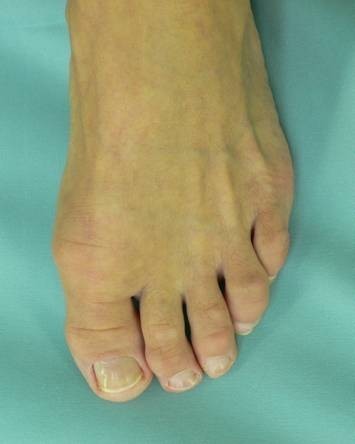

Die Patientinnen und Patienten wundern sich oft, da ihr Fuß von außen völlig normal aussieht und die Großzehe keinerlei Abweichung zeigt. Allerdings bestehen oft sehr starke Schmerzen beim Gehen und sogar in Ruhe. Wir sehen häufig solche "normal" aussehende Füße, deren Träger aber unter heftigen Schmerzen leiden. Das ist typisch für den so genannten Hallux rigidus, also die zunehmende Zerstörung des Großzehen-Grundgelenkes durch die Arthrose (Gelenkabnützung) oder durch Arthritis (Rheuma).

Der Fuß zeigt nach der Operation eine schöne und schmale Form.

Funktion und Kosmetik sind sehr zufriedenstellend - vor allem aber sind die Schmerzen weg.